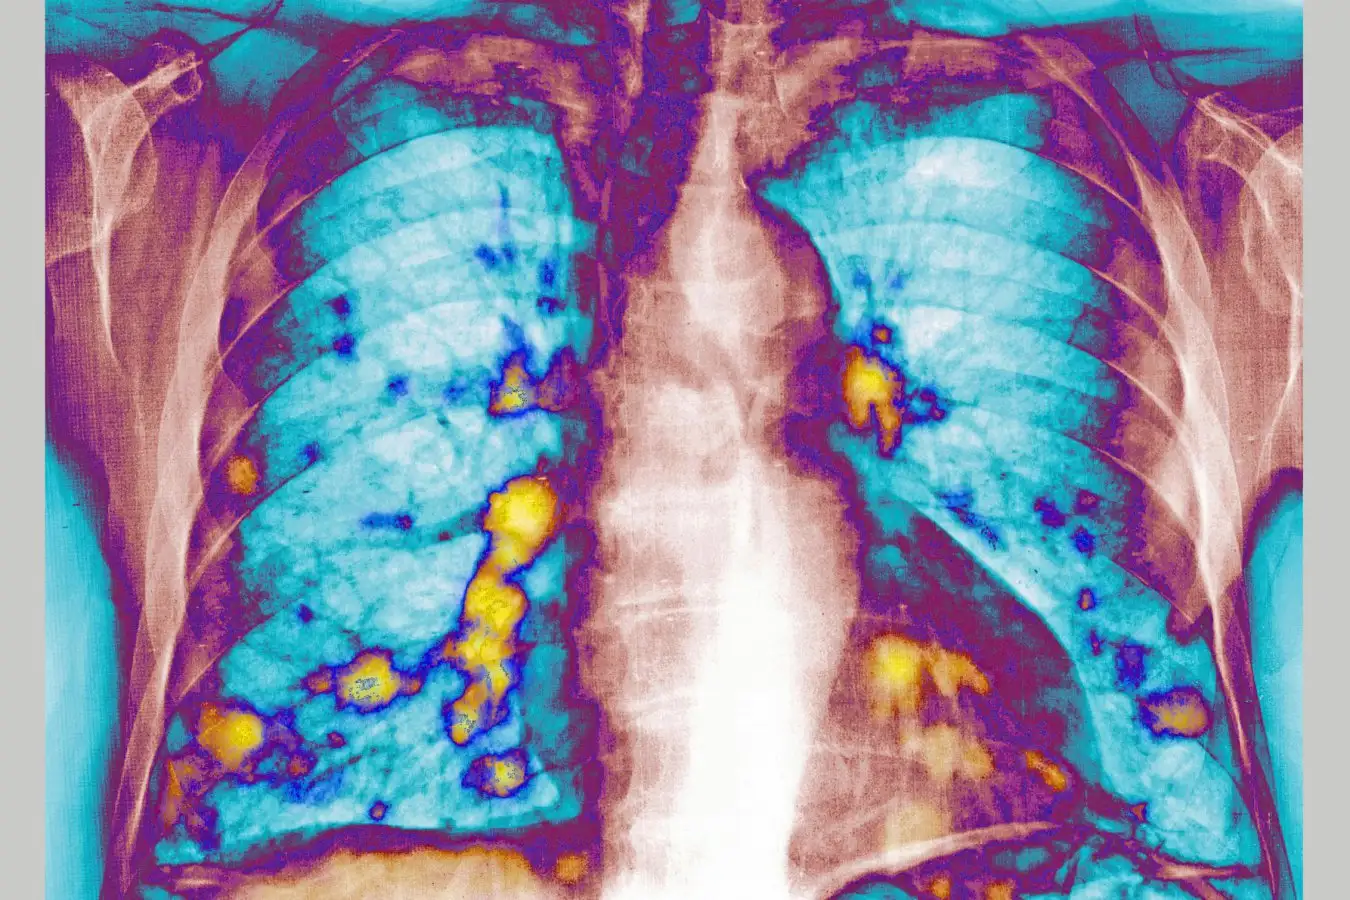

The lungs as a common site for cancer metastasis

The implications of respiratory infections, including influenza and COVID-19, on cancer metastasis are captivating researchers, especially given the lungs’ susceptibility as a common site for such spread.

The research team infected 23 mice with RSV, while 16 healthy mice were used as controls. Following a 24-hour period, all mice received injections of breast cancer cells. After 28 days, lung tumor nodules in the RSV-infected mice were reduced by 65 to 70 percent compared to controls.